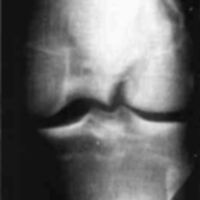

A twenty-nine year old male sustained a high caliber gunshot wound to the left knee (Fig. 4), traversing the lateral femoral condyle through the joint space and through the lateral tibial plateau. Open reduction internal fixation (ORIF) and ligamentous repairs were made. Postoperatively, the patient was placed in a standard cast brace due to the inability to provide adequate medial-lateral stability of the knee surgically (Fig. 5). The cast brace was attached to a continuous passive motion dynamic suspension system to restore and maintain motion (Fig. 6). At the time of the initial cast bracing, the patient had considerable soft tissue edema about the knee. The use of passive motion quickly reduced that swelling to the point where the cast brace provided little support. After one week, the cast brace was reapplied with the addition of a varus producing strap (Fig. 7) and the patient began ambulation training and was discharged. (If atrophy or swelling should continue, the varus producing strap can be easily adjusted to maintain force on the knee and another cast change would not be required).

Case 2